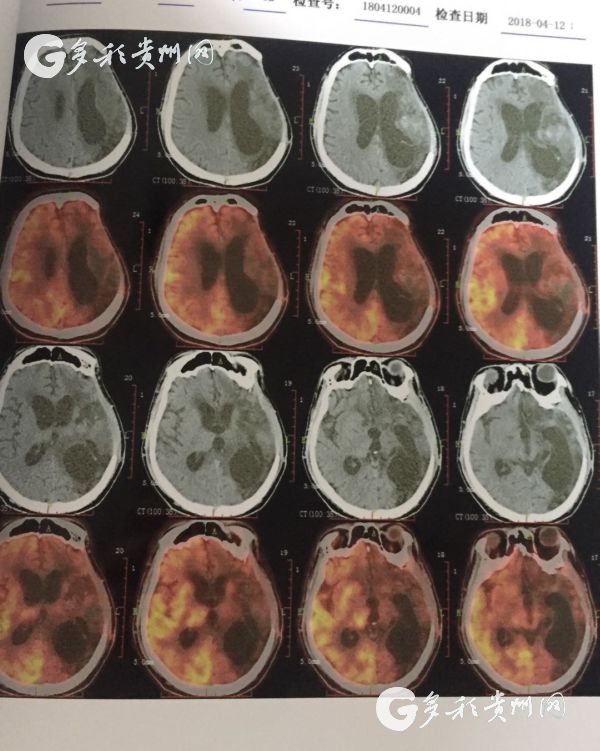

医院提供的患者脑部CT照